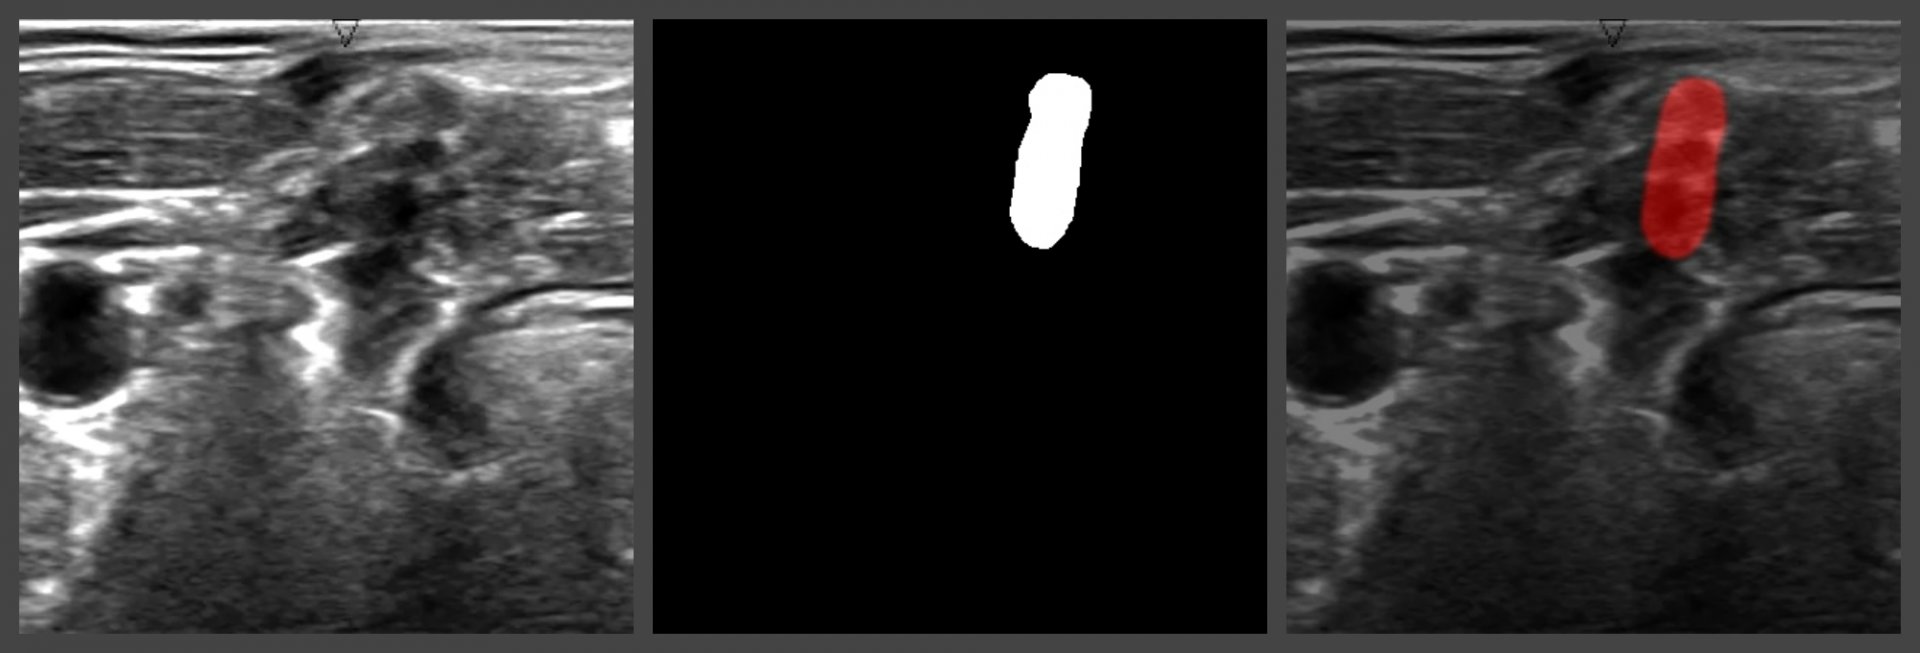

The project comes up with the solution which allows users to detect a brachial plexus on the ultrasound picture and the exact area in the patient’s body to implant the catheter. To achieve this, Computer Vision and machine learning technologies are applied.

To solve this problem, we chose UNet architecture. It is a special neural network architecture developed for biomedical images segmentation. The hyperparameters tuning has shown that the maximum accuracy in recognition is achieved through the combination of Dice + Binary Crossentropy as a loss function.

As a result, a script connected with the neural network was developed. The ultrasound image of the shoulder joint comes as an input. As an output, there is an image with the highlighted brachial plexus. Since it is a script, it can be used in any type of apps (web, desktop, mobile). The proper neural network training and setting has allowed getting ~70% accuracy in recognition.